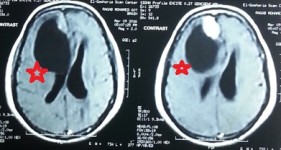

frontal lobe basement tumor